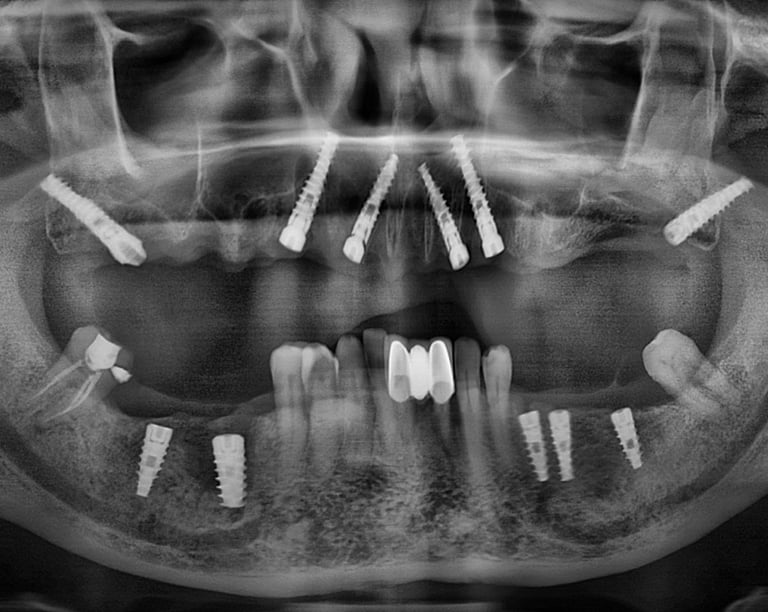

Multiple Tooth Implants

Full Mouth Implants